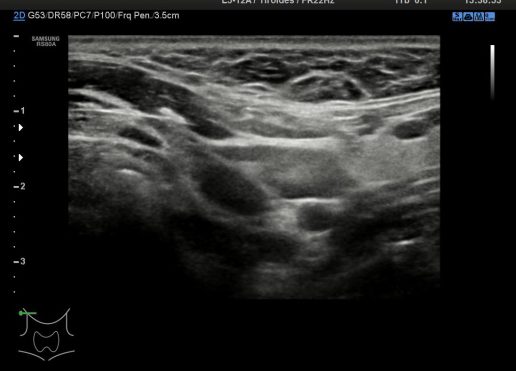

Cada región del cuello tiene que tener una foto en el estudio y que puedes ver a continuación, el objeto de esta división es la búsqueda de ganglios locorregionales, así como otros hallazgos extratiroideos que pudieran ser de interés, calcificaciones carotídeas, Tiroides ectópico, incluso las glándulas submaxilares (espacio 1 y 6 pegados al 4) y parótidas (espacio 1 y 6, debajo del pabellón auditivo u oreja).

Con esta división nos garantizamos que repasamos la parte lateral del cuello (1,2,3,6,7,8) y la parte central – superior al Tiroides (4) donde encontramos el Conducto del Tirogloso. También el espacio número 5 o escotadura supraesternal donde pueden ocultarse ganglios o restos del Timo.

Los espacios 1,2,3,6,7,8 siguen la longitud del Esternocleidomastoideo y todas las cadenas ganglionares del cuello.

Debemos permanecer muy atentos a la situación del pictograma y como se corresponde con los espacios del cuello de la foto superior.

En condiciones normales no tenemos que encontrarnos hallazgos patológicos, pero es habitual ver ganglios que no deben sobrepasar el centímetro de diámetro en eje corto para ser considerados normales, todos los hallazgos no normales deben ser registrados para posterior evaluación del Radiólogo/a.